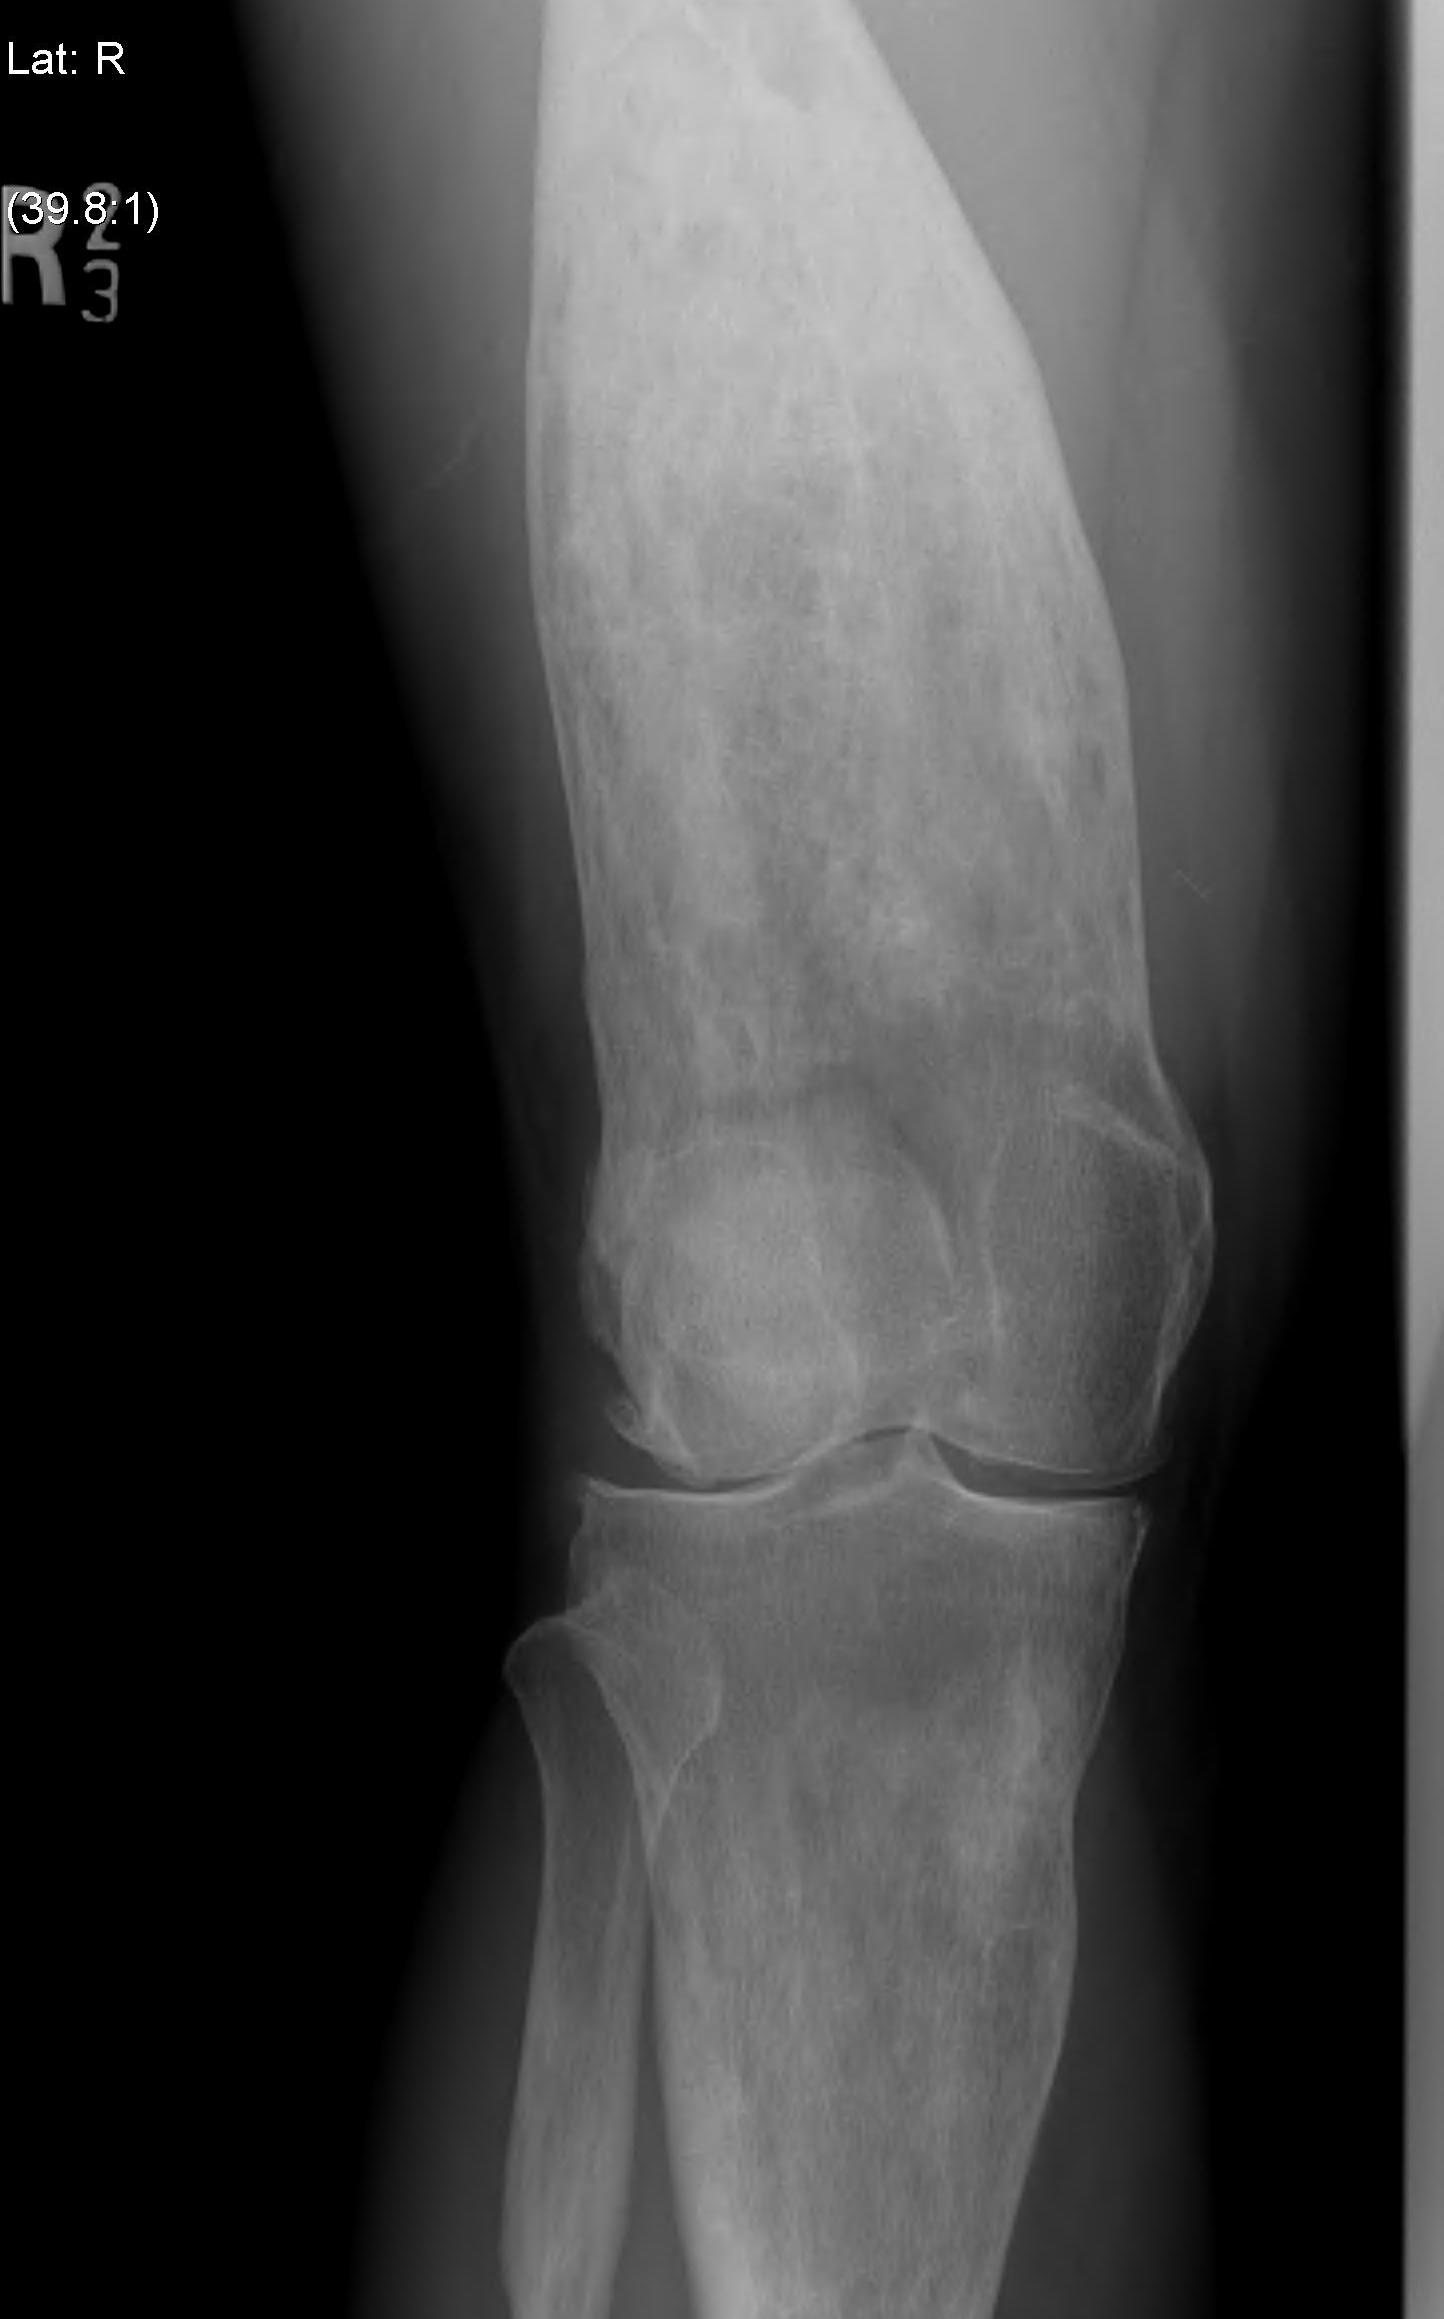

TKA

Technical issues

Exposure difficult

- patella enlarged

- risk patella tendon avulsion

Bone very hard and deformed (tibial and femoral bowing)

- difficulties with IM and EM jigs

- navigation may be advantageous

Enlarged bones

- difficult releases

- may need different femoral and tibial components

Results

- systematic review of THA and TKA in Pagets

- 19 articles and 10,000 patients

- mortality 30% at 8 years

- revision rate 2% at 7 years

Popat et al World J Orthop 2018

- 4 studies with 54 patients

- multiple intra-operative challenges: Malalignment, bone loss, soft tissue contractures

- 5% rate of patella tendon avulsion